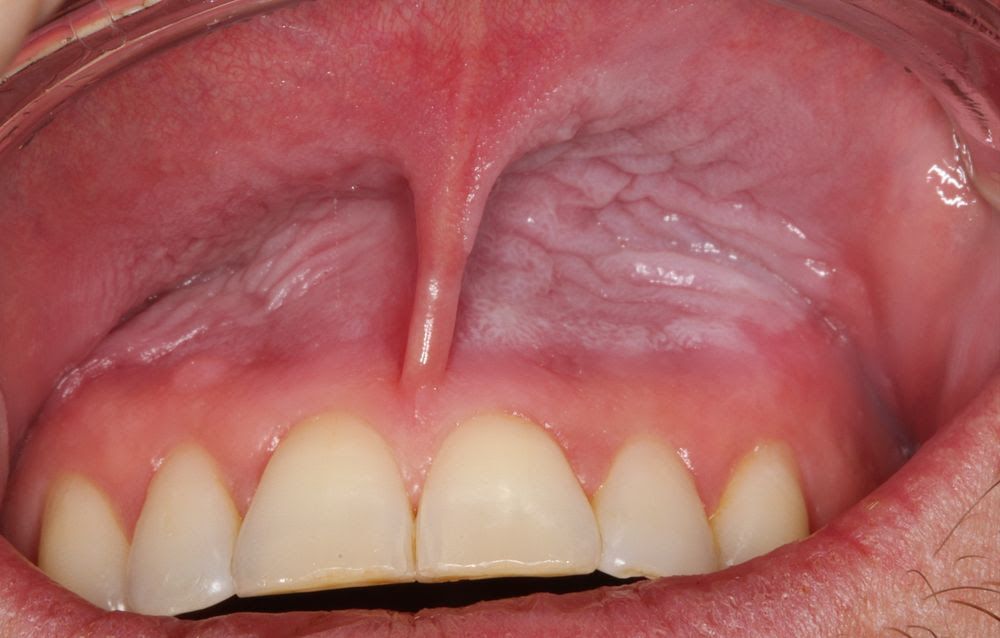

Before the trial, 43.5% of the dentists reported having irritated gums, and 95.7% had visible oral mucosal snus lesions, which are pathological changes characterized by discoloured, thickened and wrinkled mucosa due to snus use. The results showed significant improvements: the incidence of irritated gums dropped from 43.5% to 4.3%, while the presence of oral mucosal snus lesions decreased from 95.7% to 65.2%. The severity grade of these lesions was also reduced by 51.9%. After the trial, 74% of participants felt their gums were significantly healthier.